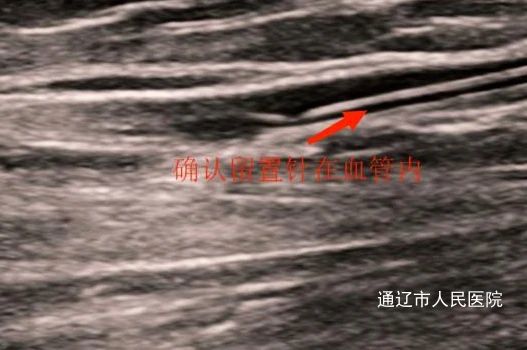

血管内置留针的超声影像

护理人员研究穿刺方法中 患者孙某,左侧乳腺癌术后,拒绝PICC置管,只能选择外周静脉穿刺,因患者血管条件极差且只能穿刺右侧手臂,每次输液都反复穿刺,十分痛苦。肿瘤内科护士刘秋月结合自身PICC置管经验与科室护理团队共同研究学习,充分评估孙某患者血管,经超声探查患者左侧上肢静脉后,利用平面外穿刺技术,消毒穿刺处、涂无菌耦合剂、左手持超声探头、右手持留置针、穿刺成功后单手送针、将留置导管稳妥送入血管内、超声显示穿刺成功!随即妥善固定,顺利完成了该例超声引导留置针穿刺。